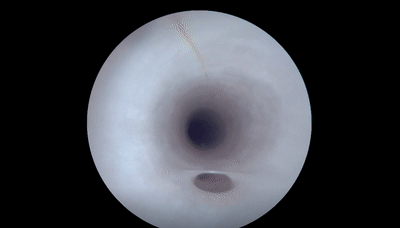

以下是VerAvanti SFE診斷急性大血管閉塞性卒中的影像

VerAvanti SFE演示